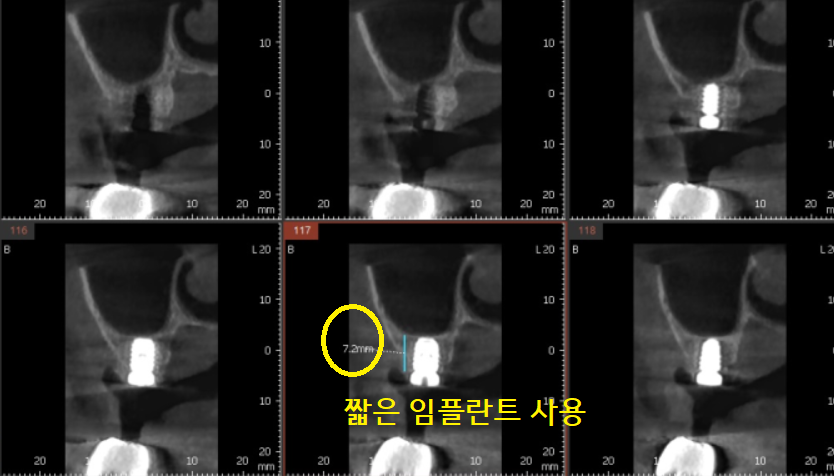

임플란트는 일반적으로 8-10mm 정도의

길이를 사용하지만

진단에서 환자분은 6mm 길이가 나왔습니다.

잇몸뼈가 거의 없으시다 보니

인공적으로 만드는 것도 한계가 있었고

짧은 길이의 임플란트를

사용할 수밖에 없었는데요.

덕풍동 치과에서

길이가 짧은 대신

넓이를 두꺼운 것으로 하여

힘을 받으실 수 있도록 하였습니다.